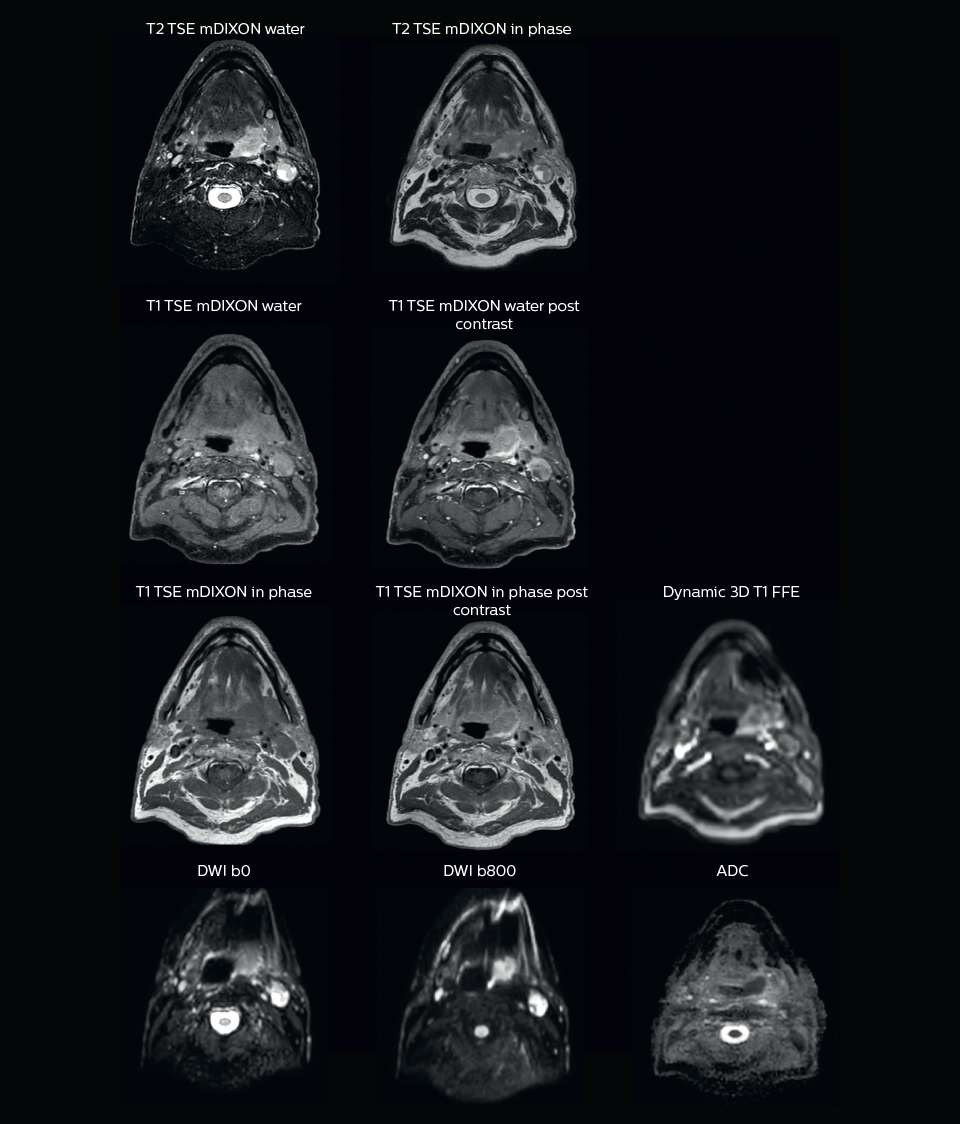

“We use pre- and post-contrast T1- and T2-weighted sequences with the fast and robust mDIXON method for fat suppression,” says Dr. Philippens. “Dynamic contrast-enhanced imaging is performed with high temporal resolution and low spatial resolution, to see the contrast agent uptake in the tumor. Diffusion weighted imaging is used qualitatively to see how the tumor extends into another structure, rather than for strict delineation.”

“In postoperative patients who have had tumor growth along the cranial nerves, we use T2-weighted gradient echo (FFE) on our 3.0T MR-RT scanner to show the nerves for target delineation and look to see if there is still tumor left.”